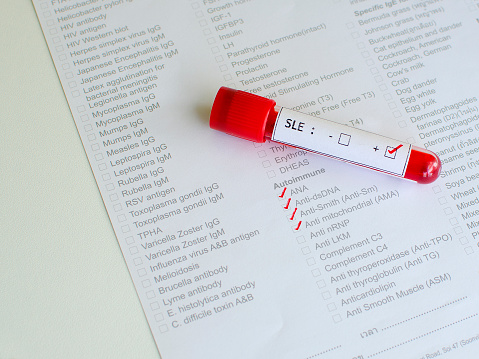

Multiple sclerosis (MS) movement and balance problems cause identified and it can help cure other autoimmune diseases. The researchers found what they call a faulty “brake” in the immune cells. This “brake” should be controlling inflammation – but it doesn’t. The new findings could also be useful in development of new targeted therapies for other ...click here to read more